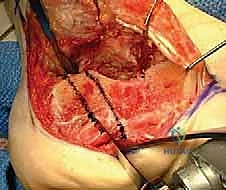

- إزالة النتوءات العظمية الضاغطة (Exostectomy):

يقوم الدكتور هطيف بإزالة الكتلة العظمية الزائدة التي تبرز من الجانب الخارجي للكعب. هذه الخطوة ضرورية جداً لتحرير الأوتار الشظوية (Peroneal Tendons) وتخفيف الضغط عن عظم الشظية، مما يقضي على الألم الجانبي ويسهل ارتداء الأحذية.